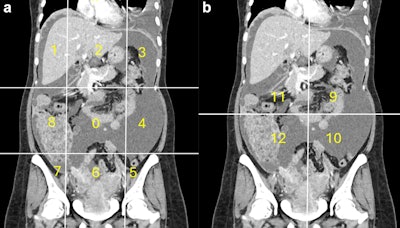

Calculation of radiological peritoneal cancer index (rPCI) adapted from Sugarbaker et al (1). (a) Coronal CT showing regions 0–8. Vertical lines are drawn along the right and left midclavicular line and the horizontal lines along the costal margin and the iliac crests. (b) Coronal CT showing regions 9 to 12. The vertical and the horizontal lines are through the umbilicus divide the small bowel and mesentery into proximal and distal jejunal and ileal regions. Images are republished under a Creative Commons license (CC BY 4.0).Calculation of radiological peritoneal cancer index (rPCI) adapted from Sugarbaker et al (1). (a) Coronal CT showing regions 0–8. Vertical lines are drawn along the right and left midclavicular line and the horizontal lines along the costal margin and the iliac crests. (b) Coronal CT showing regions 9 to 12. The vertical and the horizontal lines are through the umbilicus divide the small bowel and mesentery into proximal and distal jejunal and ileal regions. Images are republished under a Creative Commons license (CC BY 4.0).